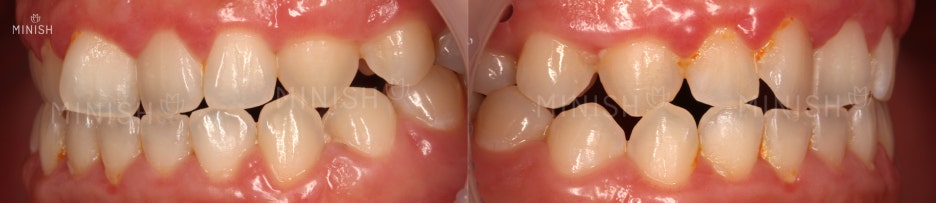

달라진 부분을 찾아보세요!

발견하셨나요? 정답은 치아입니다.

삐뚤고 어둡게 보였던 치아가 가지런하고 환하게 변했죠.

요즘 송곳니 하나 정도의 덧니는 귀여운 매력 포인트로 여겨지기도 합니다. 하지만 대문니라고도 불리는 큰 두개의 앞니가 덧니라면 인상에 부정적인 영향을 줄 확률이 더 높습니다. 정돈되지 못한 인상을 남기기 때문이에요. 또한 앞니덧니는 다양한 각도로 틀어져서 주변 이들에 가려 그림자가 지기도 하는데, 이로 인해 전반적인 색상이 어둡게 보이기도 합니다. 이러한 경우는 문제의 원인이 치아 방향 자체에 있어, 미백 치료로도 색상 개선을 기대하기 어렵죠.

틀어진 이는 청결관리가 잘 되지 않아 음식물이 쉽게 쌓이고 변색을 일으킵니다. 사진을 보시면 염증에 의해 붉게 부어있는 잇몸 상태를 확인할 수 있어요. 이때는 칫솔질 등의 약한 자극에도 출혈이 발생하고 지혈이 잘 되지 않는 문제가 동반되기도 합니다. 잇몸은 우리 이를 단단하게 잡아주는 역할을 하기 때문에 잇몸 질환 방치 시 뼈 파괴와 치아 상실로까지 이어질 수 있어 주의가 필요합니다!⭐

뿐만 아니라 전체적인 치열이 조금씩 삐뚤어져 있는 모습도 보여요! 정상적인 교합은 윗니가 아랫니를 덮으며 정교하게 맞물리는 형태를 보이는데요. 조금씩 틀어진 치아들로 인해 아랫니가 윗니를 덮거나 동등하게 맞닿는 등 부정교합의 양상을 띕니다. 부정교합은 부정확한 발음을 야기할 수 있고, 이는 면접 시에 마이너스 요소로 작용할 수 있어 중요한 개선점이 됩니다. 추가적으로 원활한 저작 활동을 방해하기 때문에 소화불량 등 전신적 문제를 일으킬 수도 있습니다. 외적인 문제를 제외하더라도 빠른 개선이 필요한 상황입니다.

질환 : 앞니덧니, 치열이상, 잇몸질환으로 인한 출혈, 충치

촬영일자 : 21.01.05 | 21.02.01

실치료기간 : 1일 (원데이)